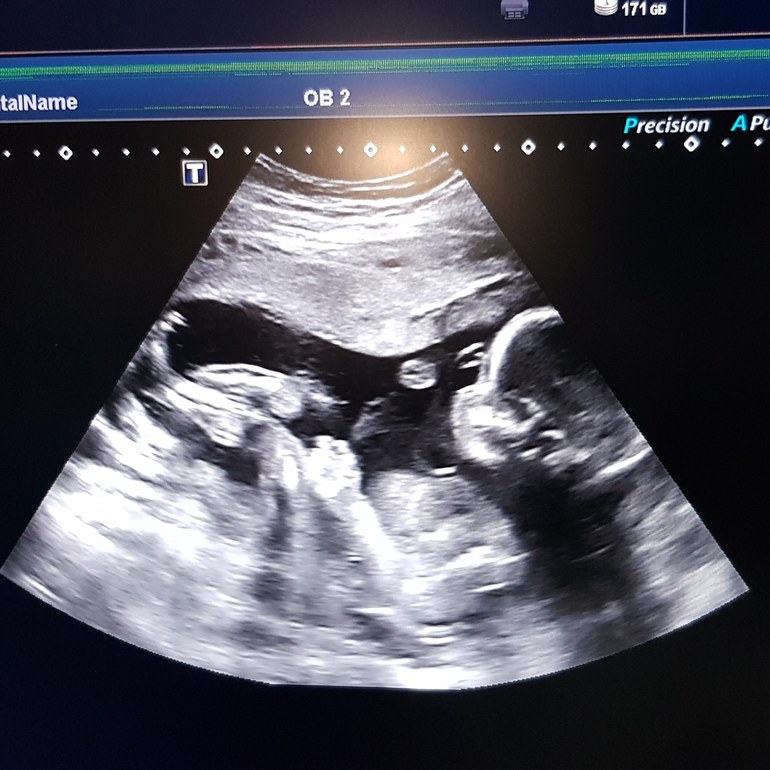

Первый скрининг

Исследование проводят с 10 по 13 акушерскую неделю. Если выбраны оптимальные сроки, на 11-12 неделе беременности, то можно узнать, какой пол у ребенка по половым бугоркам, которые уже обнаруживаются на УЗИ. У девочек центральная ось полового бугорка практически параллельна спинке, а у мальчиков угол между этими воображаемыми осями составляет около 30 градусов.

Если факторы идеально совпали, точность определения пола на этом сроке составляет 75-80 %, если же хотя бы один не соблюден, врач вряд ли станет рисковать репутацией.